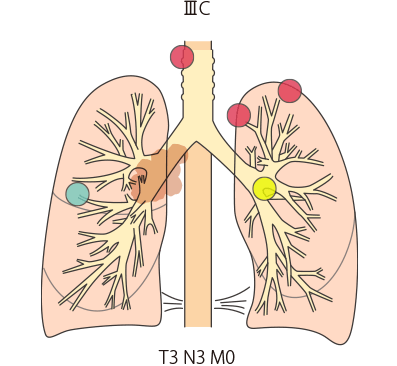

| IIIC期 | T3、T4 | N3 | M0 |

IIIB・IIIC期(ステージ3):局所進行がん

IIIC期

TNM分類でⅢB・ⅢC期と分類された肺がんは、ⅢA期よりさらに進行した状態の局所進行がんとされています。原発巣側の肺外にリンパ節転移が生じています(N2またはN3)。手術ですべてを取り切ることは難しく、手術をしてもがんが残ってしまう可能性が高いことから、基本的に手術はおこないません。

標準的な治療法としては、化学療法、放射線治療の併用が行われます。その後、免疫チェックポイント阻害薬による免疫療法が行われることもあります。

小細胞肺がんでは化学療法と放射線治療の併用が検討されます。

IIIB・IIIC期(ステージ3):局所進行がん

IIIB期

IIIC期

TNM分類でⅢB・ⅢC期と分類された肺がんは、ⅢA期よりさらに進行した状態の局所進行がんとされています。原発巣側の肺外にリンパ節転移が生じています(N2またはN3)。手術ですべてを取り切ることは難しく、手術をしてもがんが残ってしまう可能性が高いことから、基本的に手術はおこないません。

標準的な治療法としては、化学療法、放射線治療の併用が行われます。その後、免疫チェックポイント阻害薬による免疫療法が行われることもあります。

小細胞肺がんでは化学療法と放射線治療の併用が検討されます。